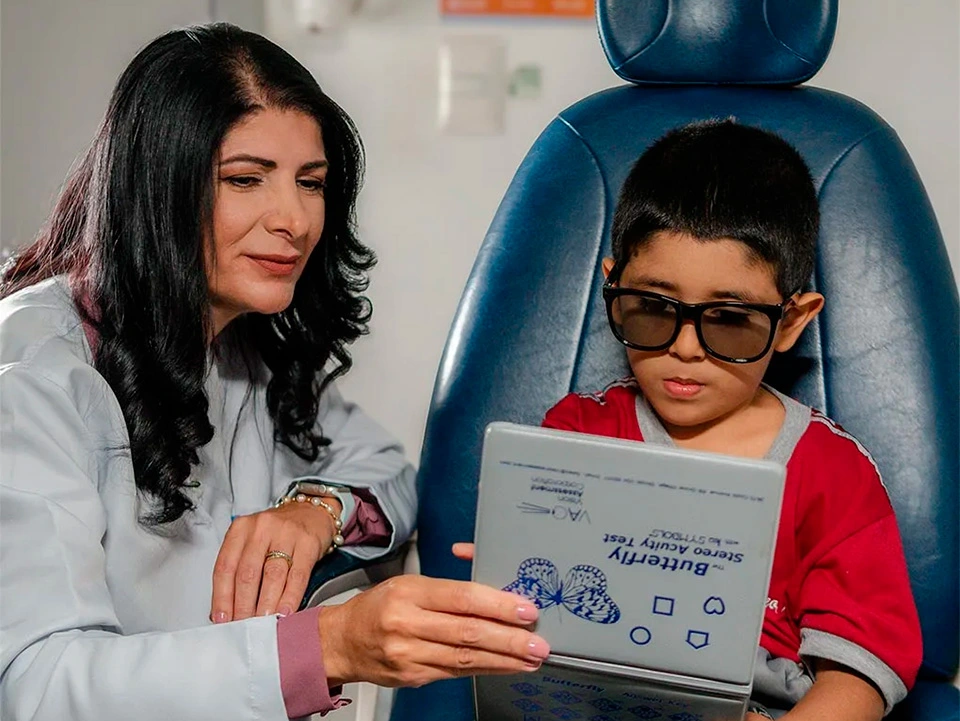

Oftalmopediatría

Oftalmopediatría

- Ambliopía

- Oftalmología Infantil